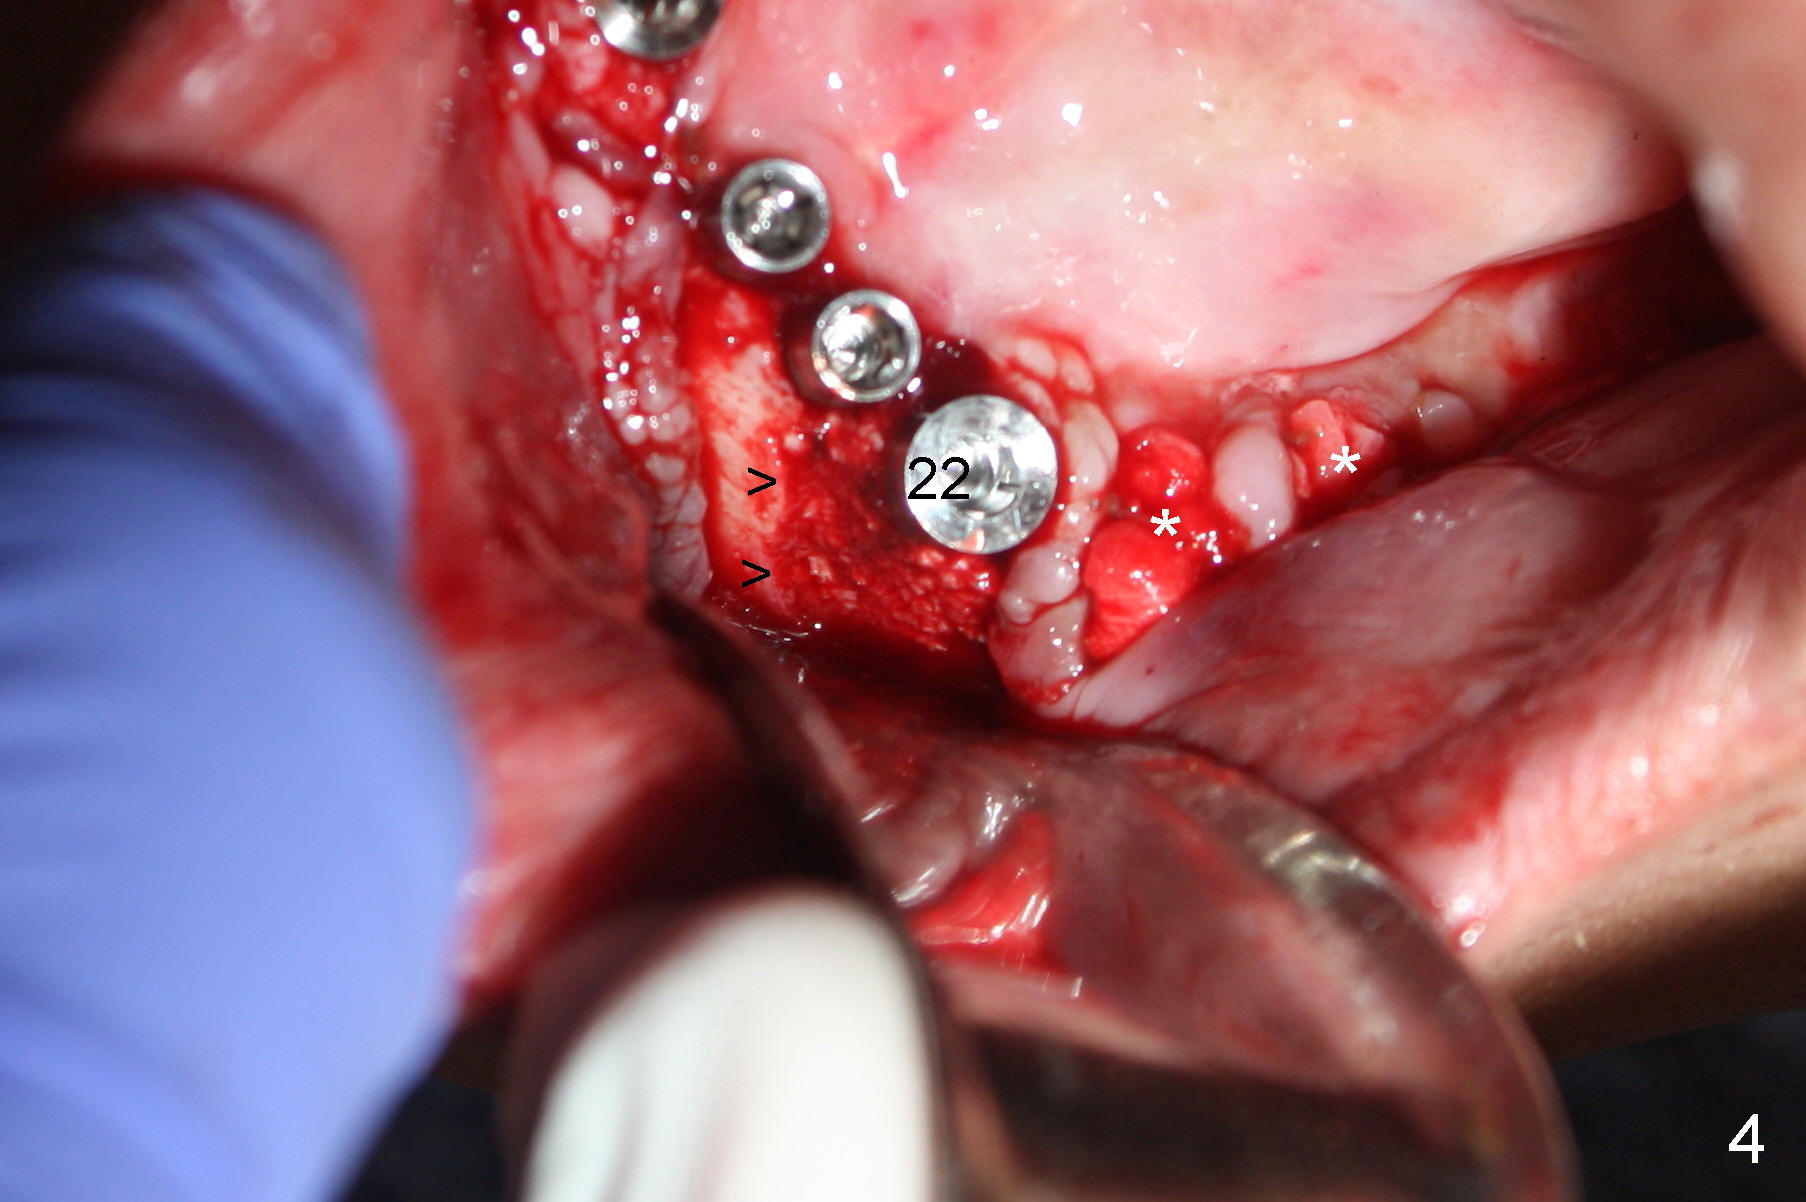

Treatment plan of the 1st surgery consists of extraction of #20 and 21/immediate implants (Fig.1 x), and placement of 4 implants between #22 and 27. Osteotomy at the extraction sites without incision (close surgery) turns out to be difficult; it appears to encroach the inferior alveolar nerve and mental loop. The sockets are subsequently bone grafted (Fig.2 *: mixture of autogenous bone and allograft). Incision is the made in the incisor edentulous region for placement of 3.5x17 mm implants (Fig.3 I).

Osteotomy is initiated through the gingiva of the healing sockets at the sites of #22 and 27 (Fig.1) with difficulty (close surgery). The incisor crest incision is extended distal to the canine areas; an accessory oblique incision is supplemented to facilitate implantation (#22: 5x14 mm; #27: 4.5x17 mm) and expose the buccal defects (Fig.3,4, open surgery). The defects are grafted (Fig.5) and covered by collagen membrane (Fig.6). The incisions are closed and abutments are placed for immediate provisional (Fig.7).

Incision (open surgery) appears to help increase surgery safety and avoid complication (nerve injury) associated with immediate implant.